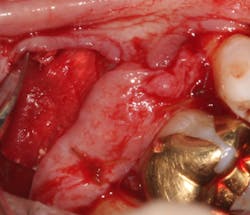

A SECT graft was harvested from the palate (figure 5), and a periosteal-releasing incision was made to ensure flap advancement (figure 6). The SECT graft was secured on the facial of Nos. 2 and 3 with 4-0 chromic gut sutures (figure 7). The osseous defect was then grafted with mineralized cortico-cancellous particulate allograft (Puros, Zimmer Biomet Dental) and covered with a collagen membrane (Bio-Gide, Geistlich Biomaterials; figures 8a and 8b). The flap was coronally advanced to completely cover the hard- and soft-tissue graft and secured with 4-0 chromic gut sutures (figure 9). The palatal donor site was sutured with 4-0 chromic gut sutures as well (figure 10).